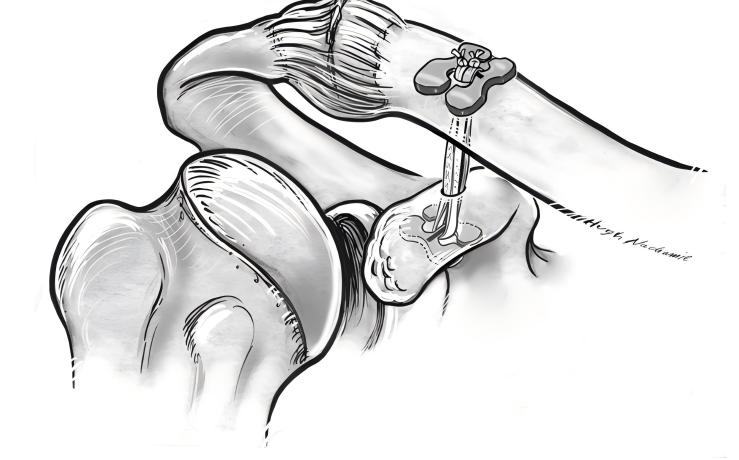

When you need advanced ac joint dislocation management, titanium plate repair offers a reliable solution. Surgeons use a step-by-step approach to restore your shoulder’s stability and function. Here is what you can expect during the procedure:

You receive general anesthesia to keep you comfortable.

The surgical team places you in a beach chair position. Your shoulders get padded, and your head tilts to the healthy side.

The surgeon exposes the surface of your coracoid and the end of your clavicle.

A fluoroscopy unit helps the team see your clavicle clearly.

The surgeon makes a 4-5 cm skin incision at the inner edge of your acromioclavicular joint.

The skin and tissue are opened to reach the dislocated joint.

Torn tissue is cleaned away. A vascular clamp is inserted along the lateral edge of your coracoid process.

The surgeon creates a tunnel and marks the outer end of your clavicle.

The guider is inserted into the lower edge of your coracoid process, following the tunnel at the clavicle mark.

The position of the guider is confirmed using C-arm fluoroscopy.

Tip: Titanium Plate repair often uses knotless constructs and Core wire tape to secure the joint. This method reduces the risk of knot slippage and improves long-term stability.

You benefit from a technique that focuses on precise placement and strong fixation. The use of titanium devices helps your joint heal in the correct position and supports early movement.